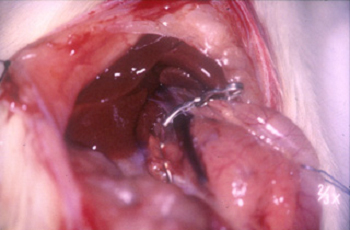

Isquemia hepática

| 1 | Puesta a punto de un modelo experimental para el estudio de la isquemia hepática normotérmica |